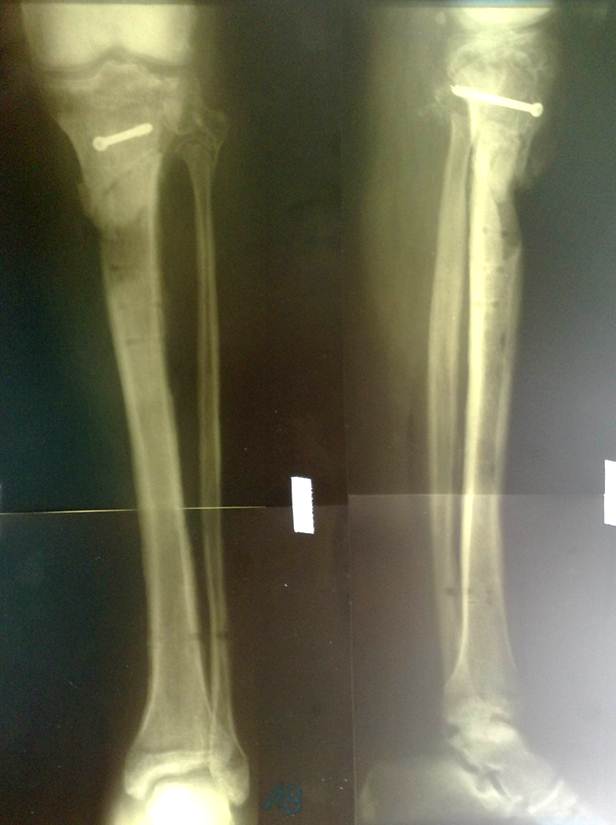

Резкая боль в бедре возникает в момент травмирования мышц, костей, суставов, связочно-сухожильного аппарата. Наиболее опасен перелом шейки бедренной кости, особенно в пожилом или старческом возрасте. Чем старше пострадавший, тем меньше вероятность его полного выздоровления. Боль настолько острая, что человек теряет сознание, появляется при таких травмах:

Сильнейший болевой синдром требует немедленной госпитализации пациента в отделение травматологи. При вывихах, подвывихах, разрывах мышц, сухожилий, связок дискомфортные ощущения не менее интенсивные. Но при таких травмах их выраженность может постепенно снижаться. В некоторых случаях человек даже не обращается в лечебное учреждение. Разорванные волокна срастаются неправильно, нередко их целостность не восстанавливается вовсе. В итоге боли в бедре становятся ноющими, хроническими, усиливающимися при ходьбе или незначительной физической нагрузке. Нередко у травмированного человека спустя несколько лет развивается остеоартроз — патология, не поддающаяся полному излечению.